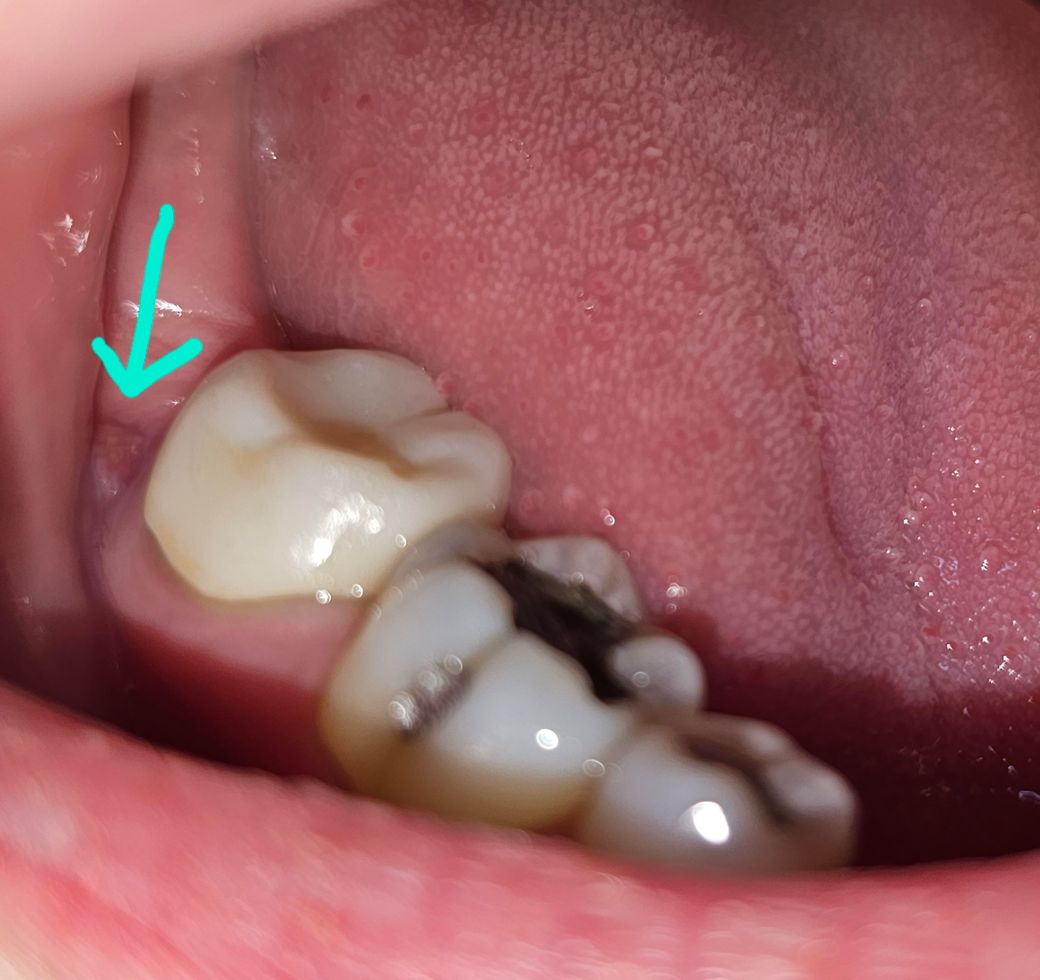

잇몸이 곪은 것 처럼 보이고 냄새가 납니다

맨 뒤쪽 치아 쪽 잇몸이 언제부턴가 이렇게 되었습니다. 보통 잇몸 쪽 문제가 생기면 며칠 있다가 금방 회복되는데 이건 몇달 동안 지속된 것 같습니다.

혀로 만지면 물러 있는, 혹은 곪아있는 듯한 느낌입니다. 통증은 전혀 없습니다.

아프지 않아 그냥 냅뒀는데 손가락으로 이쪽을 쓸어보니 냄새도 납니다. 다른쪽 잇몸에선 안나는데 이쪽에선 냄새가 꽤 나서 저 부위 때문에 나는 냄새 같습니다.

참고로 저 부근의 치아는 4년 전 쯤 사랑니 발치 후 어금니 신경치료 및 크라운 치료 받았습니다.

그후 3년 동안 치아 교정을 했고, 이 증상은 교정기를 떼고 한 두 달 후 부터 있었던 것 같습니다.

• 1번 째 사진

사진상 정확히 보이진 않으나 구강 내 병소의 양상입니다. 모양은 oral papilloma 의 가능성이 있어보이나 정확한 건 검사를 해봐야 합니다.

크라운을 한 치아 내부에 감염이 되어 치근단 질환이 생긴것으로 보입니다.

재신경치료가 필요할수 있습니다.

치아 뿌리에 금이 가서 생기는 염증이라면 발치를 해야 할수 있습니다.